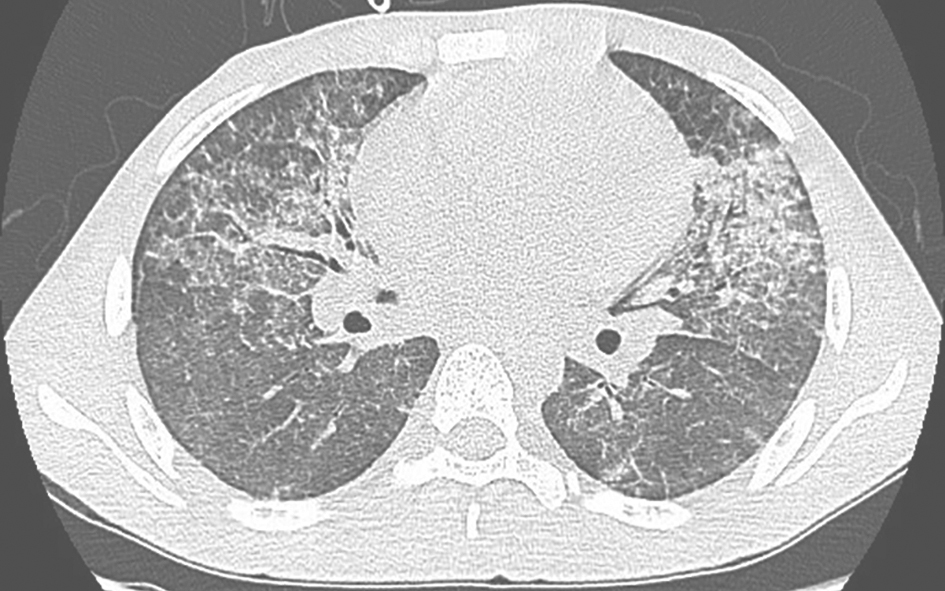

图2结缔组织疾病并发间质性肺炎胸部CT表现

胸部CT可见双肺弥漫性间质性病变,伴肺内斑片高密度影,小叶间隔增厚